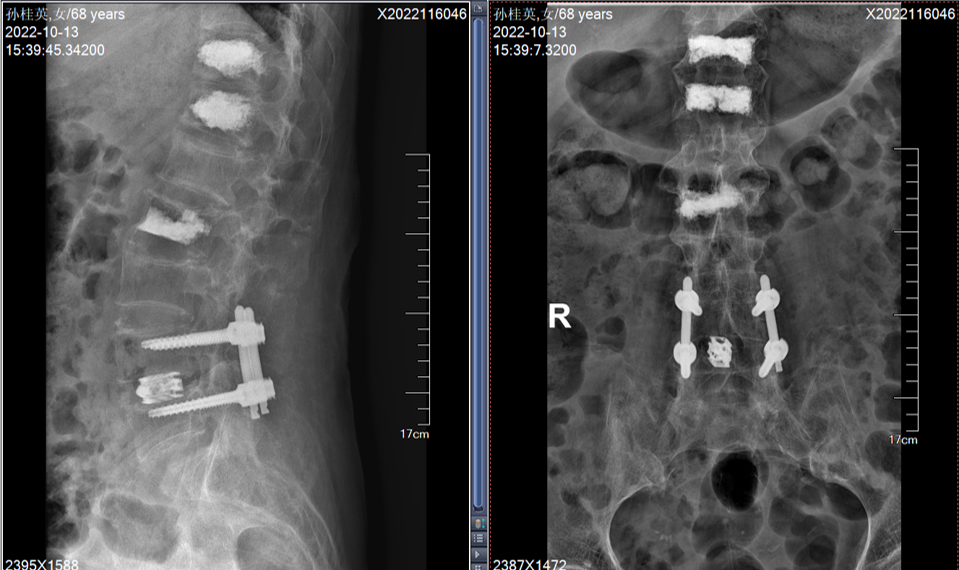

本团队率先开展腰椎微创内镜下减压融合术

有效解决了部分高龄患者不能耐受大手术(开放手术)的问题

在目前累计开展的130例内镜下腰椎减压融合手术中

有多名80岁以上患者受益

内镜下减压融合手术,既可以解决神经受压问题,又提供了长久的稳定性维持作用

手术出血控制在50ml以内,术后2-3天下床活动,避免老年患者长期卧床的并发症